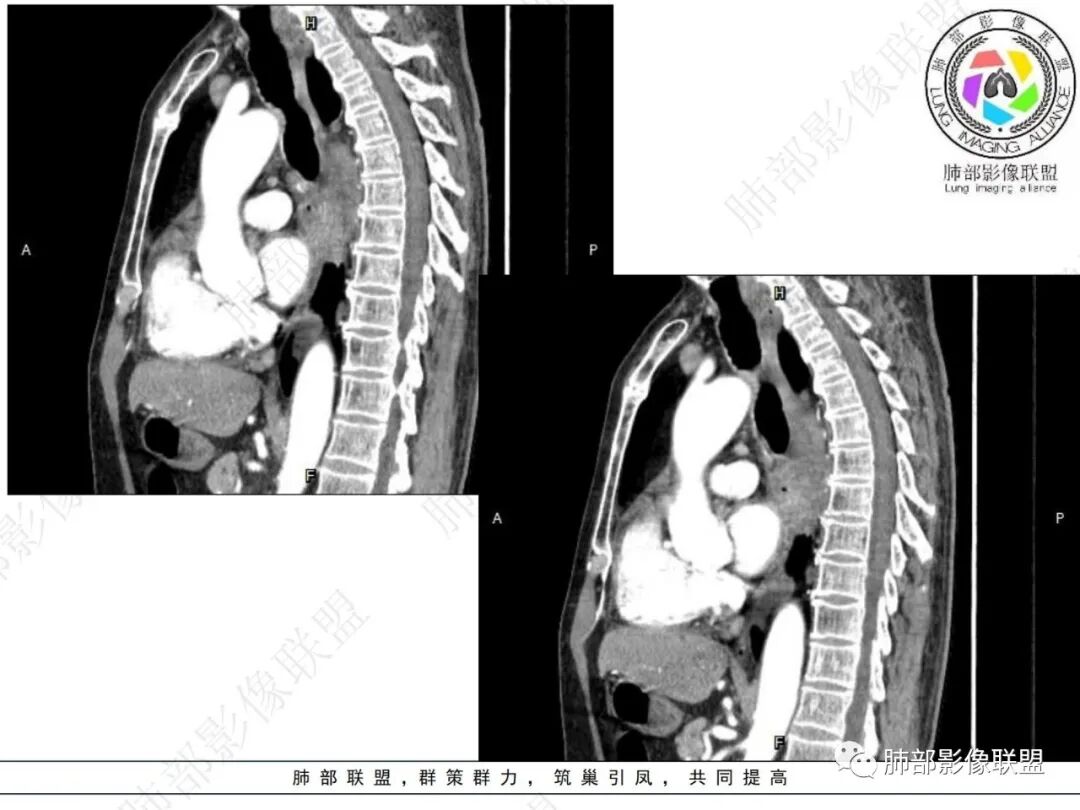

后纵隔,位于奇食窝右侧肿块,形态不规则,明显强化,右肺下叶背段支气管受压,并右肺下叶背段为主阻性炎症,右肺斜裂胸膜增厚,见多发微小串珠结节,纵隔内淋巴结肿大,与主体病灶强化性质相同,另外右下肺静脉主干边缘不规则(侵蚀破坏?),老年男性,2月前夜间刺激性干咳为主,方向恶性,纵隔旁型肺Ca,补充重建供血支气管动脉!

右肺下叶沿肺叶肺段分布斑片、条片状影,以下叶背段为显,边缘模糊,内可见支气管走行,局部支气管管壁增厚,右侧胸腔少量积液。纵隔隆突下可见不均匀软组织密度影,与周围结构分界不清,内见气体密度影,与食管及相邻右肺支气管之间未显示通道。邻近食管下段壁明显不规则增厚,增强后食管管壁明显不均匀强化,可见线样强化的连续完整粘膜影。

右肺下叶片影,气道相关,符合感染性病变。纵隔隆突下软组织密度影,异常气体影,长病程,起病缓慢,提示存在气管或食管瘘。食管镜未见明显新生物形成,临床未提供进食或饮水呛咳临床表现,综合分析应该考虑支气管瘘的形成。

对比患者3月份的CT图,原隆突下存在增大钙化淋巴结,现在出现气体影,且钙化显示不清,应想到淋巴结结核破溃成瘘可能性。

这个病例提示我们纵隔内淋巴结伴钙化或肺内结核伴钙化,可能会因患者的免疫力下降使结核复燃。